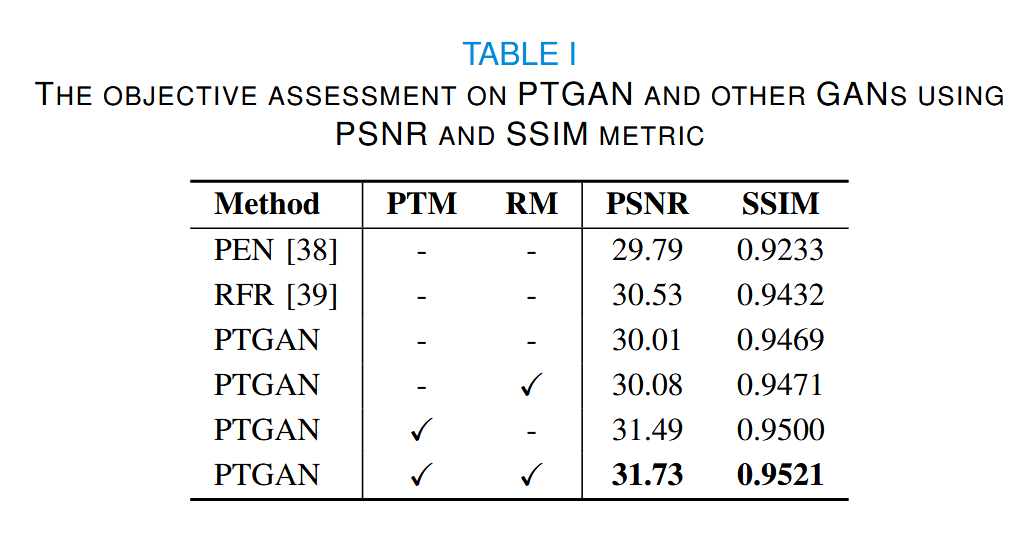

由于疾病与正常数据之间缺乏匹配,我们在定性评估 PTGAN 效果时,随机选取区域对验证集中的图像进行修复,并比较了不同方法之间的PSNR和SSIM指标,如表I所示。